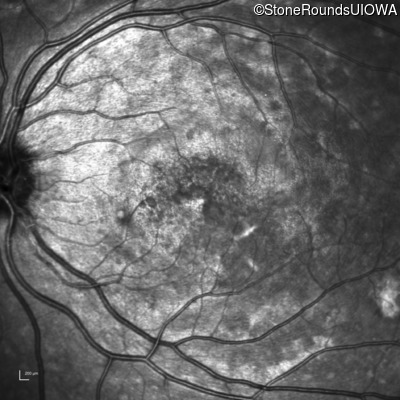

Best Disease (IIB)

Age at visit: 14 years

This 15 year old girl came to medical attention during a routine athletic vision screening when the acuity in her right eye was observed to be abnormal.

Diagnosis & molecular findings

Disease Gene Allele 1 variant(s) Allele 2 variant(s) Inheritance mode

Best Disease BEST1 Asp228Glu GAC>GAG Asn259 ins2aacAA AR